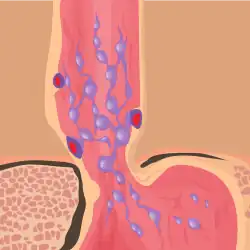

Esophageal varices are extremely dilated sub-mucosal veins in the lower third of the esophagus.[1] They are most often a consequence of portal hypertension,[2] commonly due to cirrhosis.[3] People with esophageal varices have a strong tendency to develop severe bleeding which left untreated can be fatal. Esophageal varices are typically diagnosed through an esophagogastroduodenoscopy.[4]

Varices can also form in other areas of the body, including the stomach (gastric varices), duodenum (duodenal varices), and rectum (rectal varices). Treatment of these types of varices may differ. In some cases, schistosomiasis also leads to esophageal varices.

Therapeutic endoscopy is considered the mainstay of urgent treatment. The two main therapeutic approaches are variceal ligation (banding) and sclerotherapy.

In cases of refractory bleeding, balloon tamponade with a Sengstaken–Blakemore tube may be necessary, or the use of a fully-covered esophageal self-expandable metallic stent, usually as a bridge to further endoscopy or treatment of the underlying cause of bleeding (i.e.: portal hypertension). Esophageal devascularization operations such as the Sugiura procedure can also be used to stop complicated bleeding. Methods of treating the portal hypertension include: transjugular intrahepatic portosystemic shunt (TIPS), distal splenorenal shunt procedure, or liver transplantation.